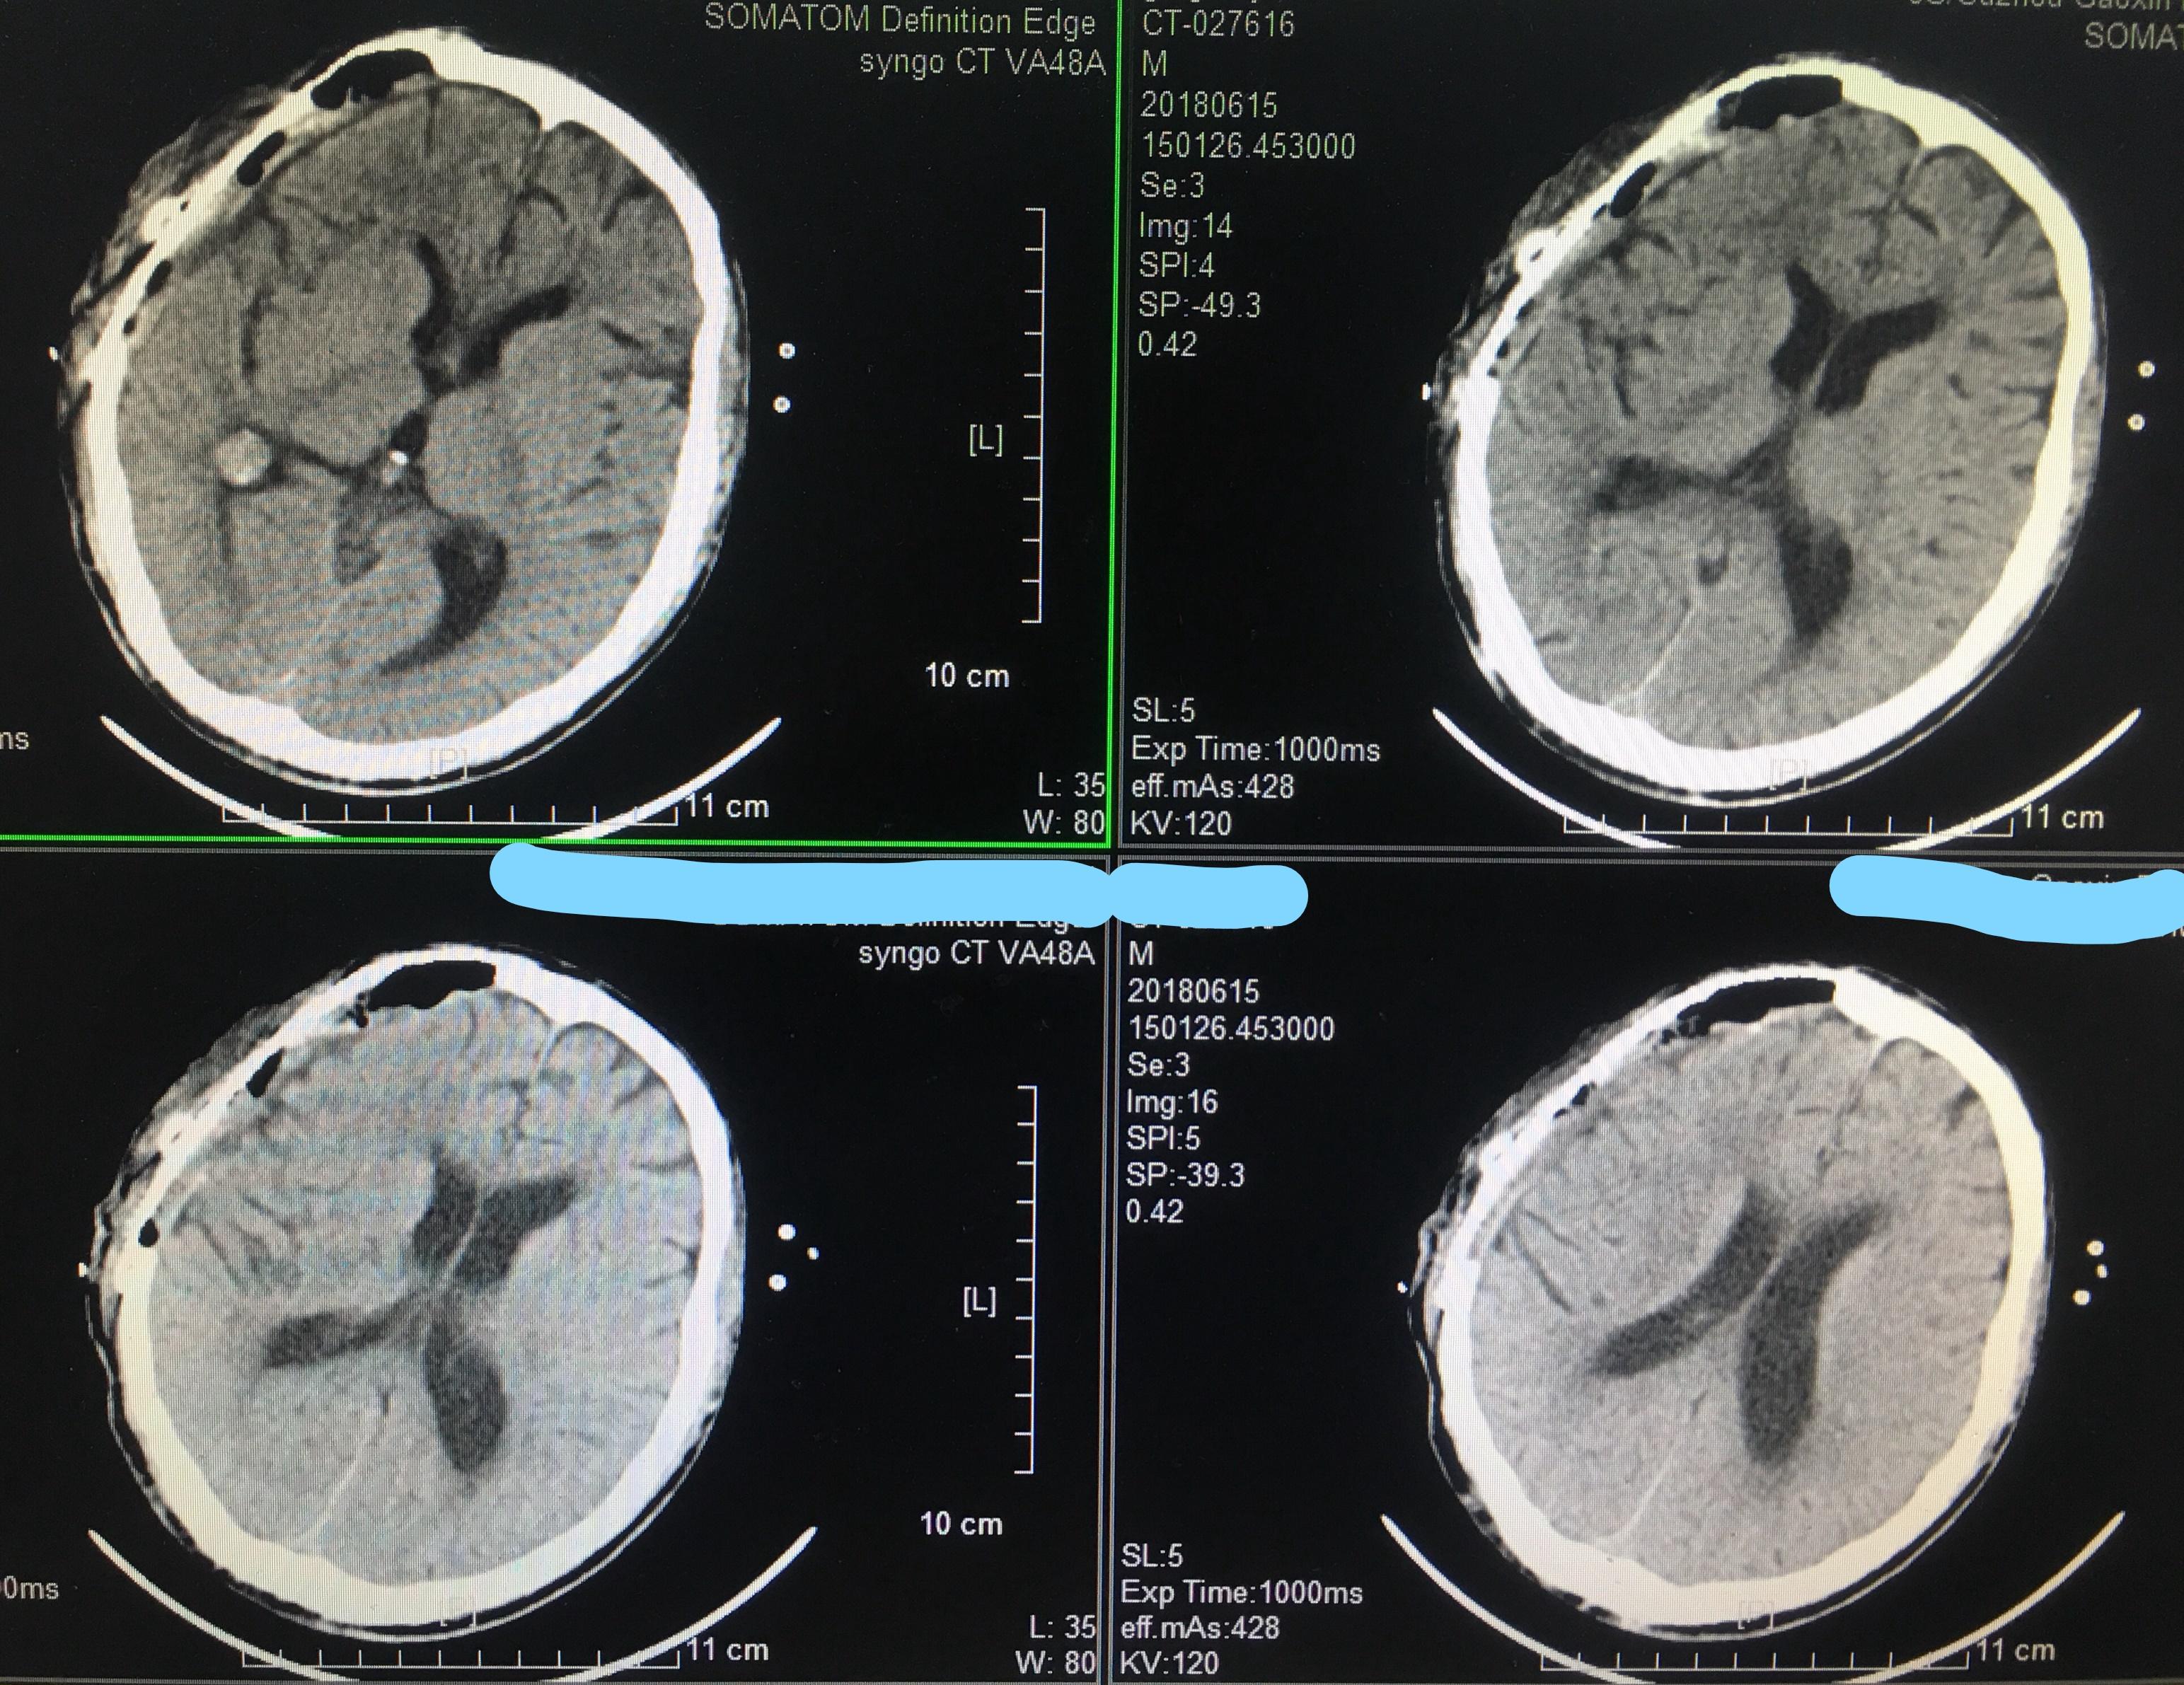

又一列硬膜外血肿的病人

图片尺寸3648x2736